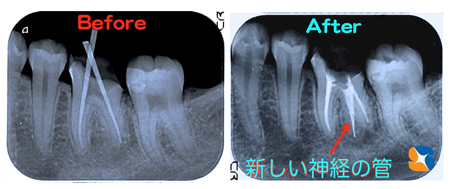

CTのお陰で神経の取り残しを回避

コラム「CTのお陰で神経の取り残しを回避」の画像